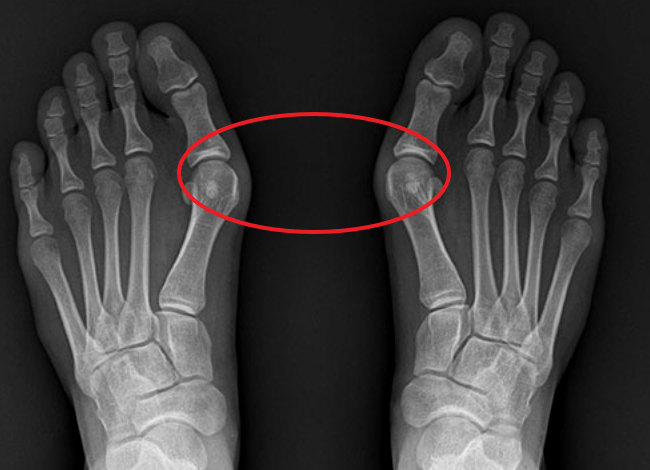

무지외반증이란 엄지발가락 관절 부분이 반대 방향인 안쪽으로 튀어나오고 엄지발가락 끝이 바깥쪽을 향해 휘어진 상태를 말합니다. 이 무지외반증 증상은 보기에도 안 좋을뿐더러 통증이 심해지면 일상생활이 힘들어진다는 고충이 있는데요.

무지외반증 증상 중 가장 흔한 증상은 엄지발가락 관절 안쪽의 돌출과 그 부위의 통증입니다. 관절 부분이 돌출이 되면 신발을 신을 때마다 자극을 받아 염증이 생기면서 통증이 발생하게 됩니다.

엄지발가락의 통증이 두 번째, 세 번째 발가락의 통증으로 이어지고 발바닥 부분에 굳은 살이 생기게 됩니다. 여기서 더 심한 경우에는 두 번째 발가락이 엄지발가락과 겹치면서 굳은살 또는 압박성 피부 궤양이 발생할 수 있습니다. 새끼발가락 관절도 돌출이 될 수 있습니다.